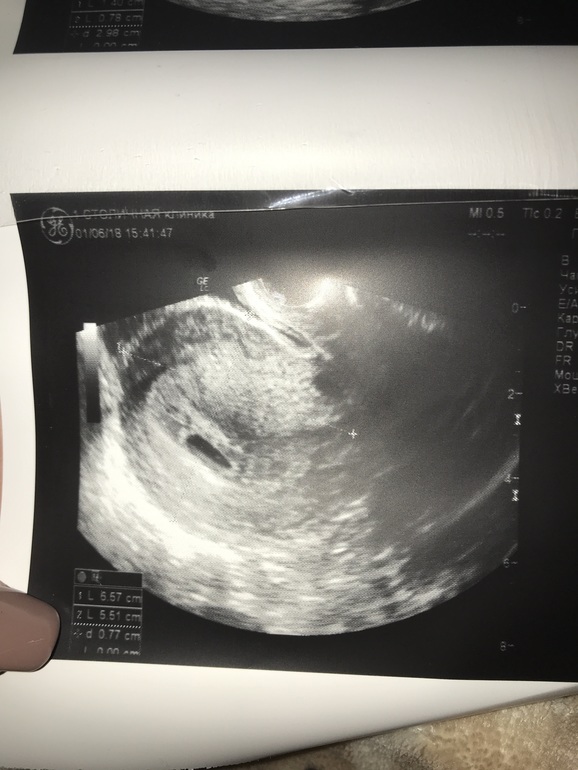

Да уж сходила на УЗИ... вначале подумала что второе плодное яйцо потом нет.. жидкость потом нет...возможно гематома... короче так я и не поняла что это жидкость или гематома, но в заключении она мне написала угроза прерывания.... начинаю пить дюф 😢

Вот это вроде гематома на или жидкость я так и не поняла